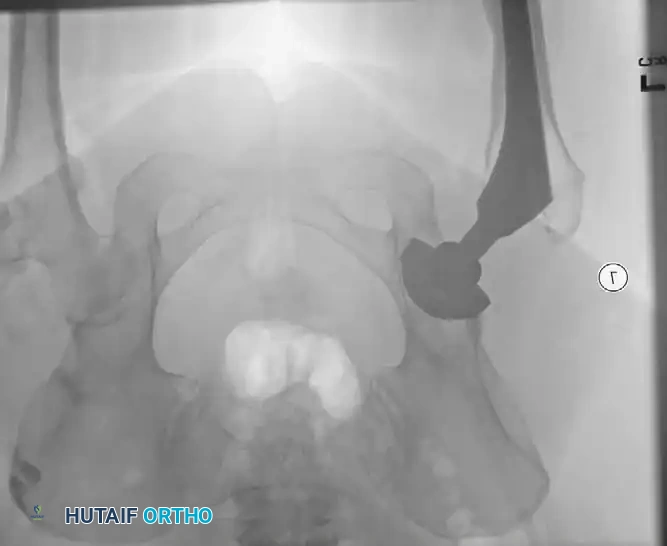

Associated Surgical & Radiographic Imaging